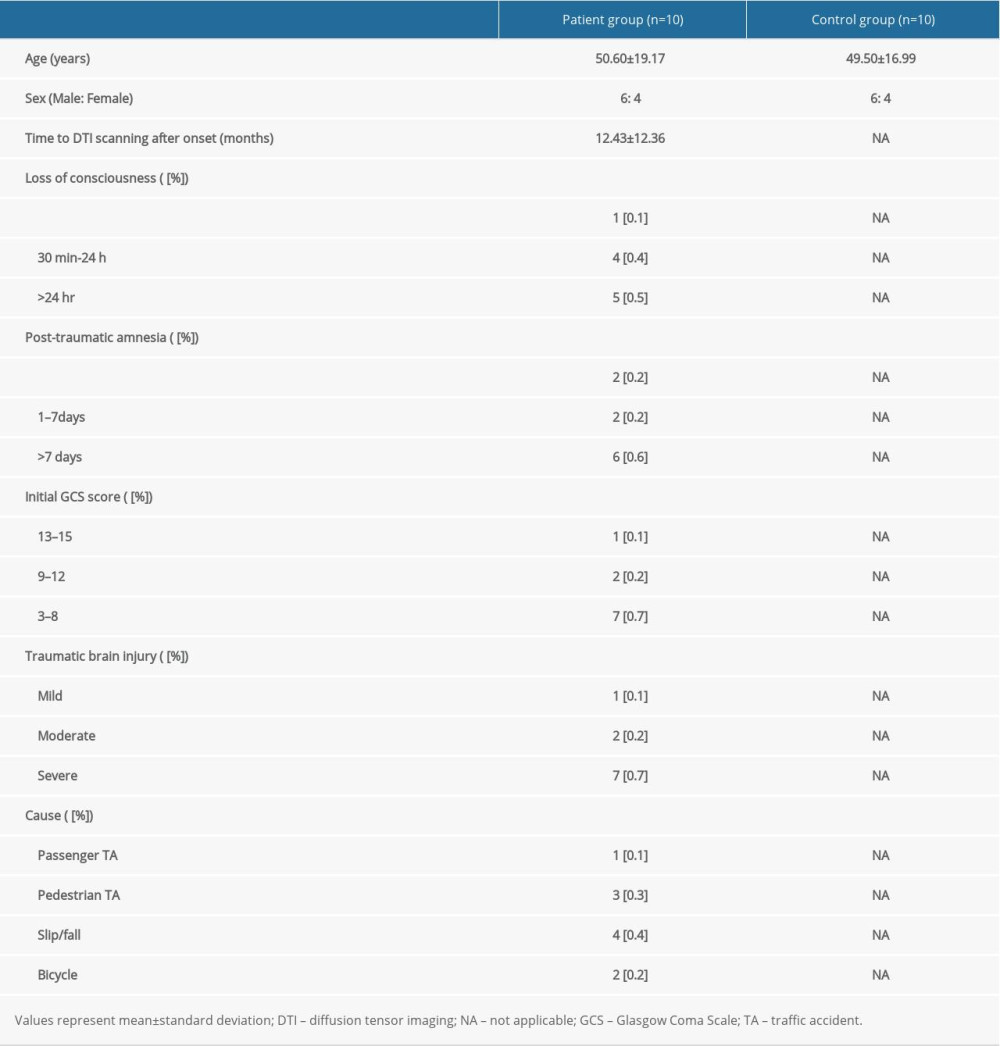

Ten patients (6 men, 4 women; mean age 50.60±19.17 years; range, 23–79 years) were recruited according to the following inclusion criteria: (1) age: 20–80 years; (2) no history of previous head trauma or neurologic or psychiatric disease; (3) SAH due to head trauma, but no other definite brain lesion in the brain parenchyma (such as intracranial hemorrhage, intraventricular hemorrhage, hydrocephalus, or subdural hygroma), which was confirmed by a neuroradiologist; and (4) DTI data obtained after 4 weeks from hemorrhage onset. Ten age- and sex-matched healthy control subjects without previous history of psychiatric or neurologic disease or head trauma (6 men, 4 women; mean age 49.50±16.99 years, range 22–74 years) were also recruited as a control group. The demographic characteristics for the patient and control groups are listed in Table 1. Age or sex distribution identified no significant difference between the patient and control groups (P>0.05). This retrospective study was conducted following the requirements of the Declaration of Helsinki research guidelines and the recommendations of the Institutional Review Board of Yeungnam University Hospital. Signed informed consent was obtained from all of the subjects, and the study protocol was approved by the Institutional Review Board of Yeungnam University hospital (ethics approval number: YUMC-2021-03-014). In the case of patients with cognitive disorder or visual problem due to traumatic SAH, informed consent was provided through the caregiver.

Table 1. Demographic characteristics for the patient and control groups.

Table 1. Demographic characteristics for the patient and control groups. Table 2. Results from the region of interest-based analysis of fractional anisotropy values of the patient and control groups.

Table 2. Results from the region of interest-based analysis of fractional anisotropy values of the patient and control groups. Table 1. Demographic characteristics for the patient and control groups.

Table 1. Demographic characteristics for the patient and control groups. Table 2. Results from the region of interest-based analysis of fractional anisotropy values of the patient and control groups.